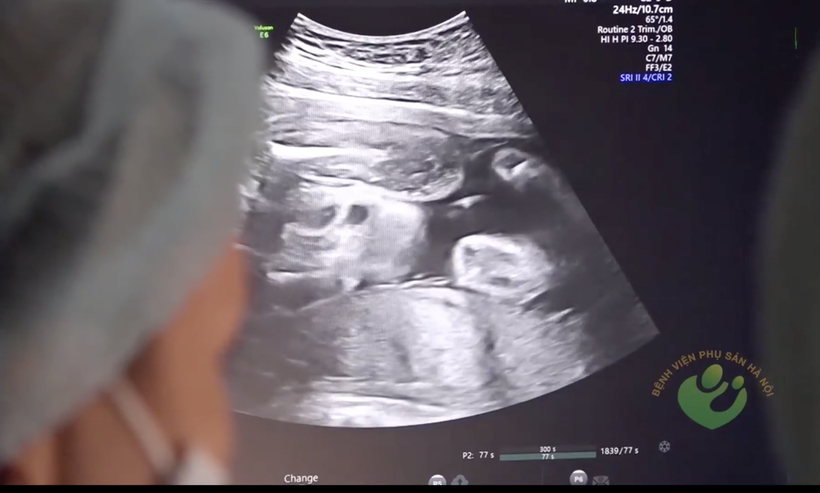

![]() |

| Bác sĩ quan sát hình ảnh siêu âm thai nhi của sản phụ (Ảnh: BVCC) |

Sau khi truyền ối, sản phụ sẽ được các bác sĩ giám sát, theo dõi chặt chẽ các dấu hiệu nhiễm trùng. Việc truyền ối có thể tiến hành nhiều lần để đảm bảo thai nhi được phát triển một cách tốt nhất và phục vụ cho việc quản lý thai nghén.